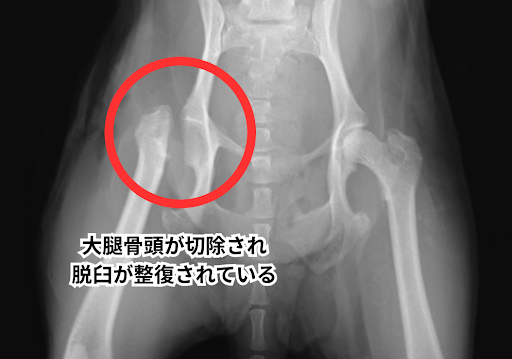

飼い主さまと相談の上、今回は大腿骨頭切除術を行い、脱臼していた大腿骨頭の切除を行いました。

手術後のレントゲンでは大腿骨頭が切除され股関節脱臼が整復されていることが分かります。

手術は無事に成功し、術後は糖尿病の管理をしながら5日ほど入院治療を行いました。

術後の経過は順調で、退院から1週間後の再診時には、手術した足を地面に軽く着いて歩くことが出来るようになりました。